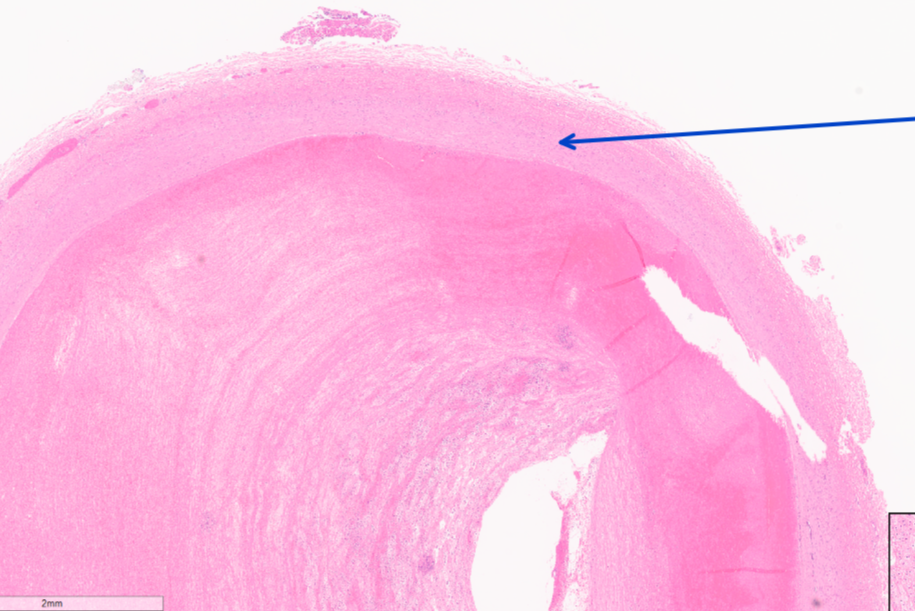

Q

This is from the umbilicus of a cat, identify this structure:

A

artery wall

How well did you know this?

1

Not at all

2

3

4

5

Perfectly

24

This is from the umbilicus of a calf, What is occuring here?

luminal thrombus

25

Identify this structure:

lines of Zahn

26

What is this?

fibrin